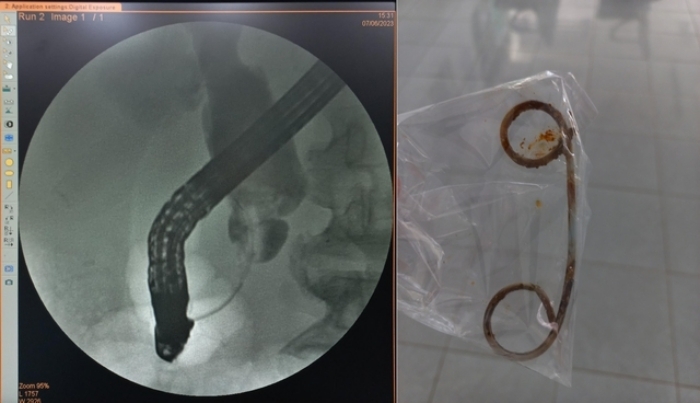

Ảnh chụp đường mật bị hẹp đoạn cuối ống mật chủ và stent bị tắc do để quá lâu. (Ảnh: BVCC)

Thông tin từ người nhà cho biết, người đàn ông có tiền sử mổ sỏi ống mật chủ cách đây 6 năm và đã đặt stent dẫn lưu do bị sẹo hẹp đường mật làm tắc mật tại 1 cơ sở y tế ở TP.HCM.

Sau đó, ông khám 1 lần và đã thay stent, lần tái khám tiếp theo thì quên nên đã để stent trong đường mật suốt 2 năm nay.

Sau khi can thiệp dẫn lưu mật bệnh nhân đã nhanh chóng hết sốt, giảm đau bụng, tình trạng lâm sàng cải thiện rõ rệt.